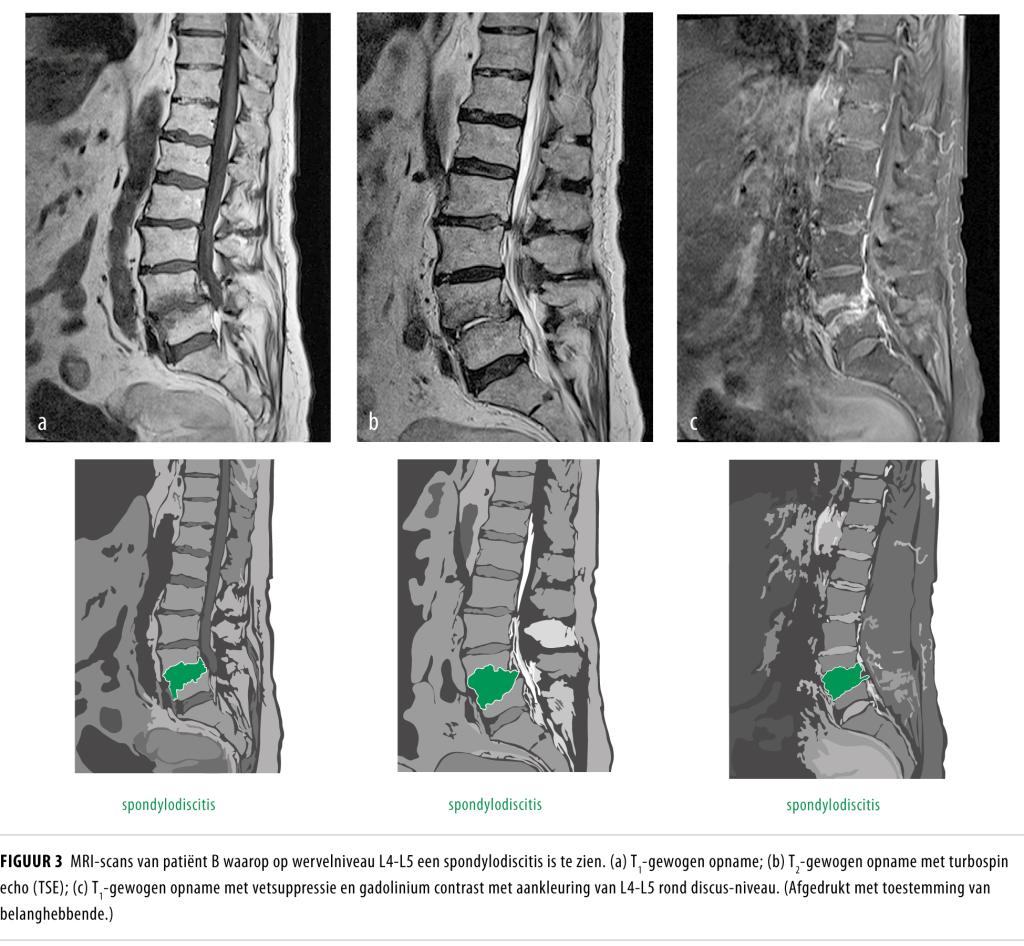

De casus van patiënt kwam ook aan de orde tijdens de oncologiebespreking, waar het sterke vermoeden werd uitgesproken dat patiënt wervelmetastasering had met een bijkomende infectie anders dan spondylodiscitis. Het antibioticum werd vervolgens gestaakt, waarna de ontstekingswaarden weer stegen en de rugpijn toenam. Op zoek naar een eventuele primaire tumor werd een FDG-PET-CT-scan verricht. Hierop zagen wij een beeld dat paste bij spondylodiscitis op meerdere wervelniveaus (T5-T6, T11-L1 en S2-S3) (figuur 2). De bloedkweken, afgenomen vóór aanvang van de antibiotica, bleven negatief.